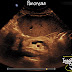

Case 22: Pancreas Ultrasound Anatomy

Pancreas Ultrasound Anatomy Landmarks help find pancreas are: Abdominal Aorta Inferior Vena Cava Superior Mesenteric Artery Splenic Vein S...